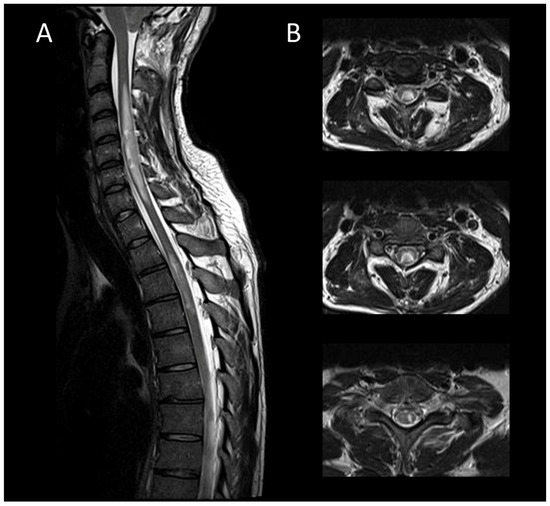

3.3.1. Spinal Cord Infarction

3.3.2. Spinal Dural Arteriovenous Fistula

3.3.3. Spinal Cavernous Malformation